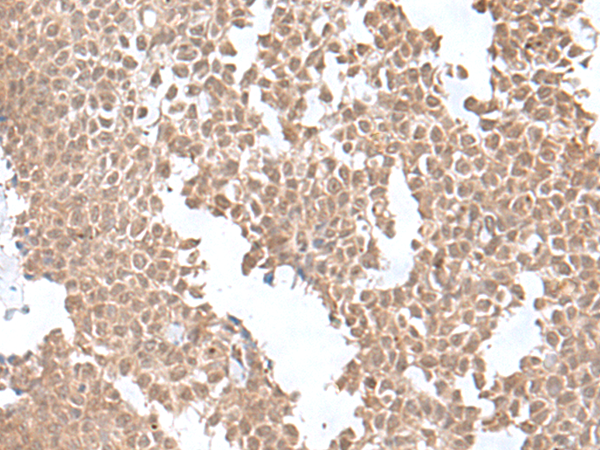

ELISA, IHC |

IHC positive control: |

Human ovarian cancer and Human gastric cancer |

IHC Recommend dilution: |

50-300 |